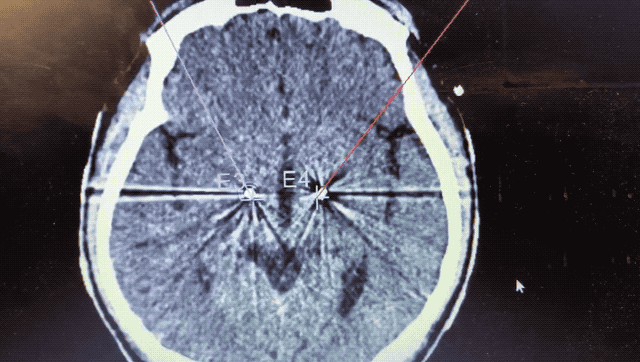

alt text

術(shù)中監(jiān)測(cè)到典型核團(tuán)信號(hào)

順利檢測(cè)到典型的核團(tuán)信號(hào)后,再次植入刺激電極到相應(yīng)位置,測(cè)試后即可完成單側(cè)的電極植入。對(duì)側(cè)只需借助機(jī)器人再次定位,并將檢測(cè)電極、刺激電極依次植入,最后,還需將刺激器植入患者胸前皮下。根據(jù)術(shù)后CT顯示,本手術(shù)雙側(cè)植入電極的位置與術(shù)前規(guī)劃路徑完全吻合,患者開(kāi)機(jī)后,起搏器會(huì)開(kāi)始沿刺激電極向患者核團(tuán)實(shí)施高頻電刺激,以減輕疾病癥狀,提高患者的生活質(zhì)量。

術(shù)后CT顯示雙側(cè)電極植入位置與規(guī)劃完全吻合